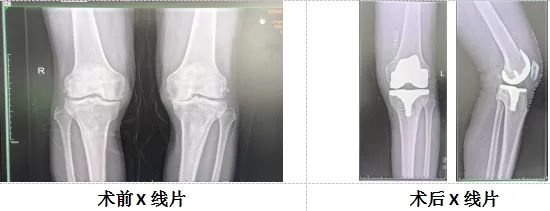

手术病例:患者张某某,67岁,因“双膝关节反复疼痛4年余,加重1月”来诊。4年间,患者尝试过多种治疗方法,如口服药物、外用膏药、针灸理疗、关节腔注射等,病情反复加重,效果不满意。后慕名来我院治疗,骨伤二科朱祥挺副主任医师接诊患者后,详细查体、完善检查、充分评估后,建议患者行“人工全膝关节置换术”。随后,骨伤二科主任张永祥带领全科医师进行了详细的术前讨论,并制定了周全的手术方案——保留后交叉韧带的全膝关节置换术,此方案得到了北京大学人民医院李虎教授的充分认可和悉心指导。

在李虎教授和骨伤二科(骨关节运动医学科)团队的紧密协作下,手术圆满成功。术后,患者感觉良好,将继续在医护人员精心护理与指导下,快速康复。此次手术成功积累了宝贵经验,未来,骨伤二科(骨关节运动医学科)将持续发力,携手专家提升医疗水平,为枣庄百姓健康贡献更多力量。保留后交叉韧带的优点:一、以提供膝关节置换术后关节的本体感觉,术后体验感更加轻松,真正实现“自然膝”。二、在提高膝关节活动度的同时增加膝关节的稳定性。三、增加股四头肌力量,有助于改善爬高功能。四、吸收和分散剪切压力,降低假体的松动率。